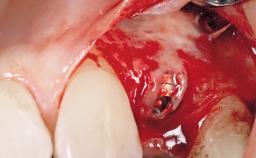

Immediate Placement of an Implant in a Maxillary Left Central Incisor Site

A 33-year-old female patient presented with an upper left central incisor that required extraction after a failed endodontic therapy. The tooth had been traumatized when the patient was a teenager and had undergone several endodontic treatments, including two apicectomy procedures. The patient was in good health and did not smoke. Clinical examination showed that the patient had a high lip line. In full smile, the gingival margins of the upper teeth were visible to the first molars. The gingival margins of central incisors 11 and 21 were only just showing. Examination of tooth 21 confirmed that the tooth was mobile and had hypererupted by 1 mm.

Type of Implants One-Piece

Bone Augmentation Horizontal|Simultaneous

Augmentation Materials Xenogenous|Membrane

Placement Protocol Immediate implant placement

Tooth Site Maxillary incisor or canine